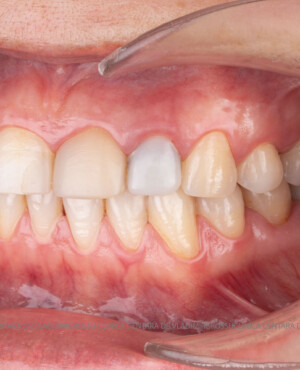

Restaurări cu coroane din zirconiu vs fațete ceramice

Atât fațetele ceramice (Emax sau 360) cât și coroanele din zirconiu sunt soluții estetice eficiente. Fațetele sunt indicate pacienților cu o poziție dentară relativ uniformă și dinți vitali, deoarece implică șlefuirea minimală a smalțului (0,4–0,7 mm) și fixarea adezivă sub coferdam. În cazurile cu dinți tratați endodontic, coroane pigmentate, proteze pe implanturi sau când este necesară o creștere semnificativă a ocluziei, se preferă coroanele din zirconiu.